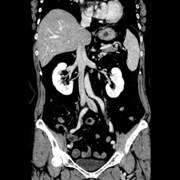

Discovery CT750HD(CT750HD)では、新しい検出器素材として人工ガーネットを用いた「Gemstone™」を採用されています。このGemstone™は、X線に対する発光効率、変換速度ならびに減衰速度、残光特性が従来のものと比較して、飛躍的に性能が向上しています

X線を検出するために、ガドリニウムオキシサルファイド=GOS(固体シンチレーターの材料)が使用され、X線撮影(増感紙)やX線透視(X線テレビ)等のX線検出装置に利用されてきました。しかしながら、近年CTスキャナーに求められる高空間分解能の向上を更に進めるためには、既存の素材では今まで以上の発光効率、変換速度ならびに減衰速度、残光特性を得ることには限界がありました。